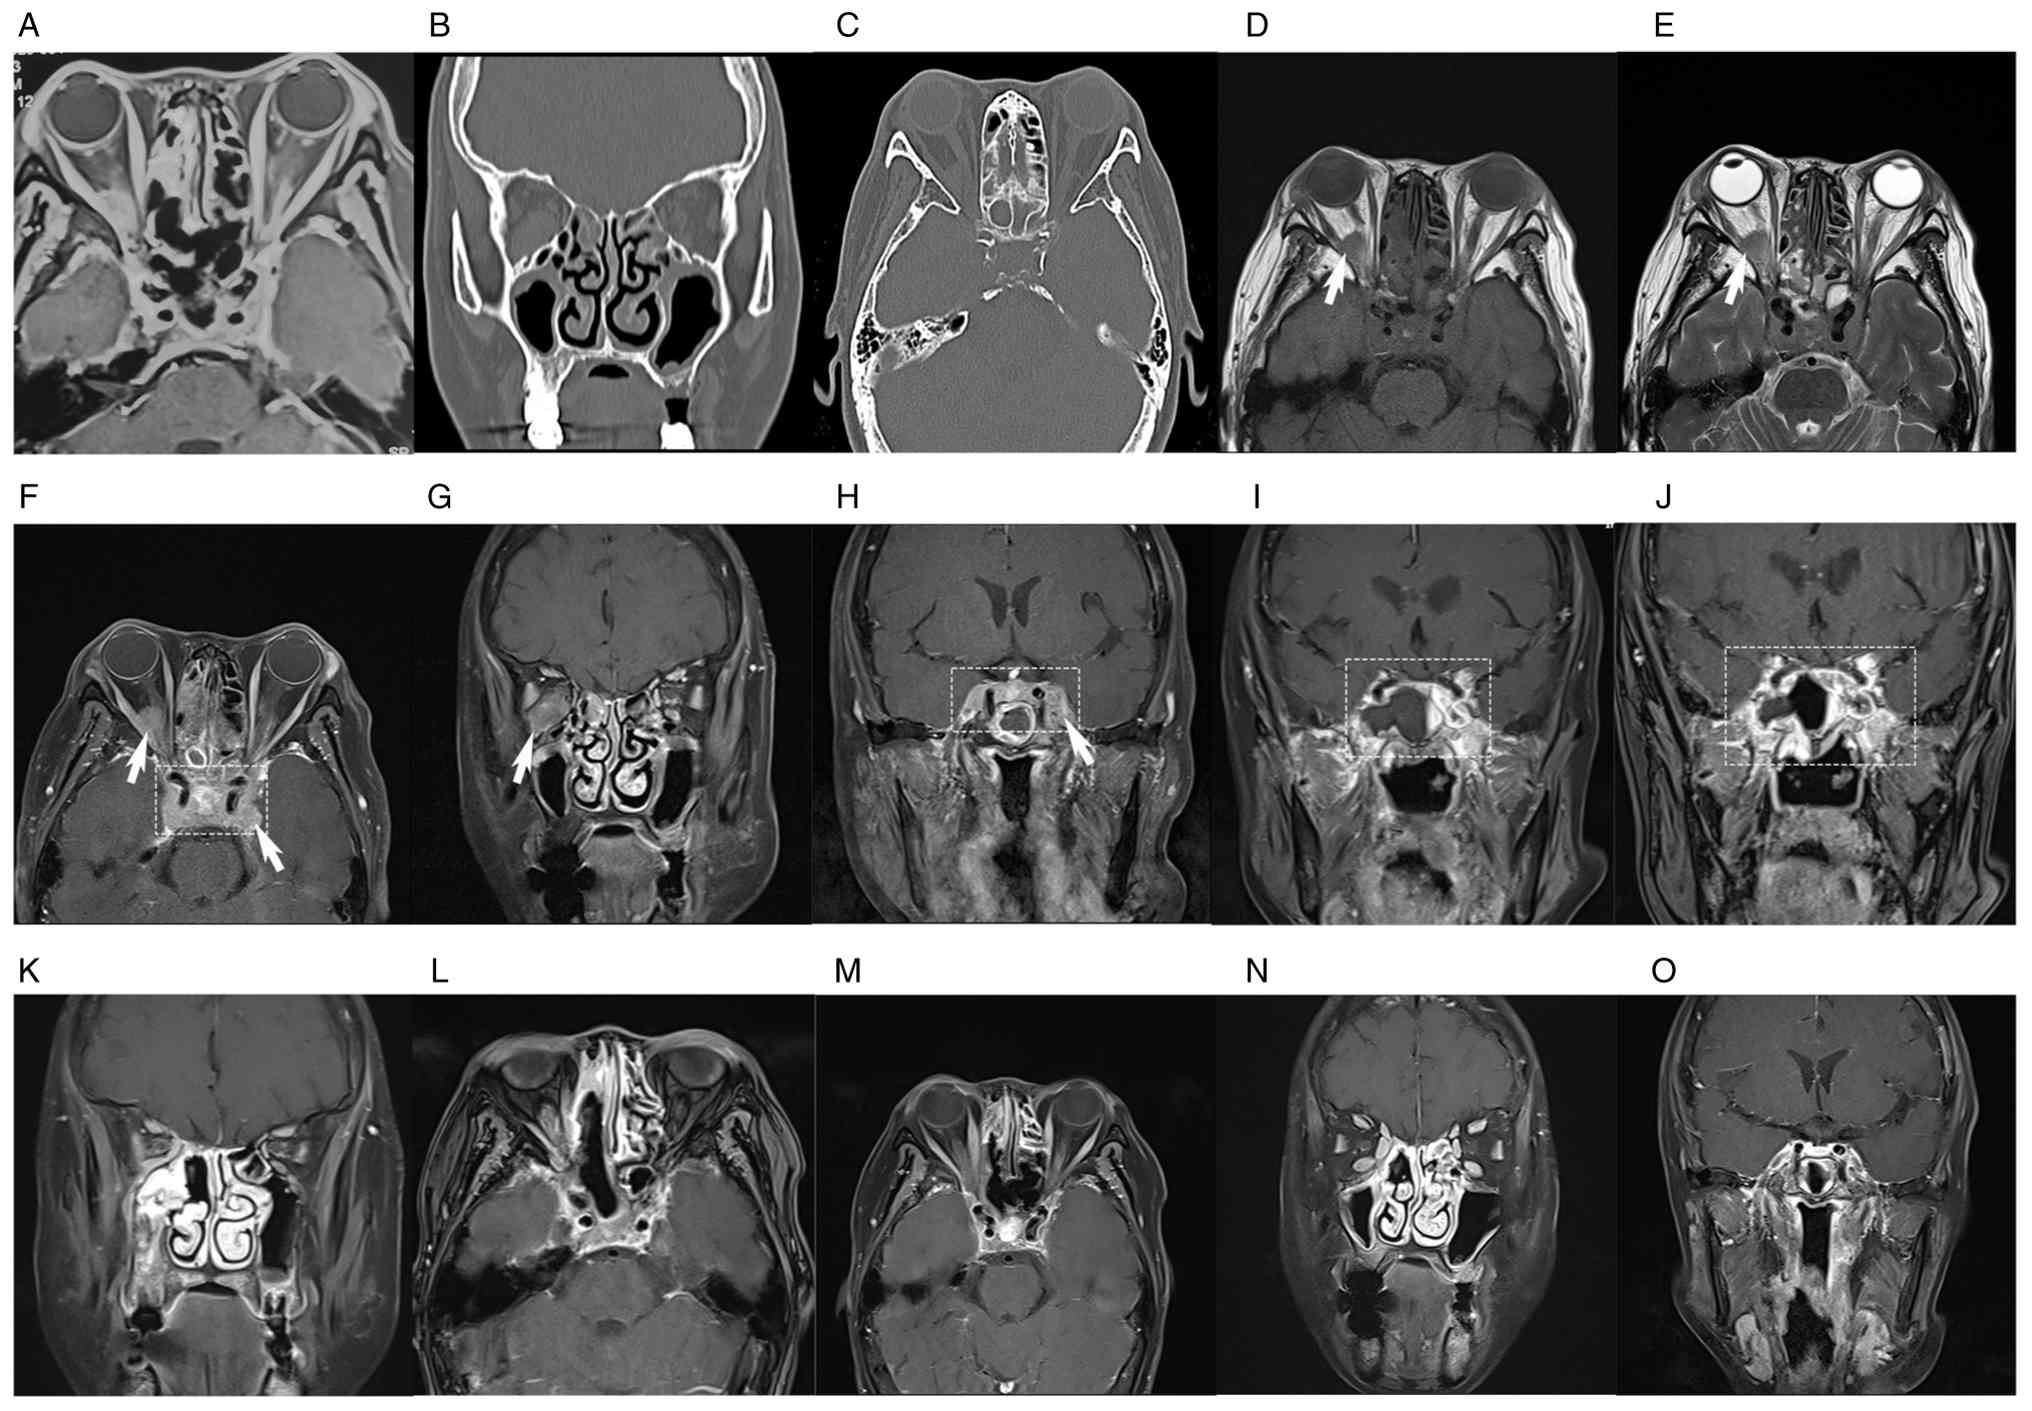

Routine cerebrospinal fluid (CSF) tests and biochemical indices were normal. CSF analyses, including ink staining, Gram staining, acid-fast staining, and bacterial and fungal cultures, were all negative. CSF pressure was 105 mm H2O (80–180 mmH2O), and no tumor cells were identified on CSF pathological examination. Orbital MRI revealed a 15.9×5.9 mm lesion at the right orbital apex, while contrast-enhanced MRI showed abnormal thickening and enhancement of bilateral CSs, extending to the adjacent dura mater and clivus (Fig. 1A). A CT scan of the skull base, orbit and sinuses showed no bony destruction and adjacent hyperostosis (Fig. 1B and C). An idiopathic orbital inflammatory pseudotumor was initially suspected, and intravenous methylprednisolone pulse therapy was initiated (120 mg on days 1–3 and 80 mg on days 4–6) but was discontinued due to severe gastrointestinal symptoms. The ptosis and complete external ophthalmoplegia of the left eye showed no improvement. Over the subsequent week, the patient developed complete bilateral external ophthalmoplegia, severe bilateral blepharoptosis completely covering the pupils, and bilateral fixed and dilated pupils (OD, 5 mm; OS, 6mm). Follow-up MRI revealed multifocal abnormal enhancement in multiple areas, including the bilateral CSs, right orbital compartment, sinonasal cavities, clivus and marrow cavity of the left pterygoid process (Fig. 1D-H).

MRI findings and CT scan images of the

patient. (A) MRI of patient at the first visit. (B) Coronal CT scan

of the skull base, orbit and sinuses at the first visit. (C) Axial

CT scans of the skull base, orbit and sinuses at the first visit.

(D-H) Baseline MRI before initiation of the R-CHOP regimen. (D)

Axial T1-weighted imaging showing a 1.2×1.6×0.9-cm lesion at the

right orbital apex (white arrow). (E) Axial T2-weighted imaging.

(F) Axial and (G) coronal T1 fat-suppressed gadolinium-enhanced MRI

images demonstrating masses located in the right intraconal orbital

space (white arrow), left intraorbital optic nerve sheaths, nasal

cavity, paranasal sinuses and bilateral CSs (rectangular marquee).

(H) Coronal contrast-enhanced MRI of the bilateral CSs (rectangular

marquee). (I) MRI of bilateral CSs after 3 cycles of R-CHOP

combined with a BTK inhibitor. (J) MRI revealing an enlarged CS

lesion after 4 cycles of R-CHOP combined with a BTK inhibitor

compared with that after 3 cycles of the regimen (rectangular

marquee). (K) Coronal contrast-enhanced MRI of skull base, orbit

and sinuses after six cycles of R-CHOP combined with BTK inhibitor

and two courses of HD-MTX. (L) Axial contrast-enhanced MRI of the

CS, orbit and sinuses after 6 cycles of the regimen. (M) Axial

contrast-enhanced MRI of the CS, orbit and sinuses post-treatment

corresponding to images F before treatment. (N) Coronal

contrast-enhanced MRI of the orbit and sinuses post-treatment

corresponding to images G before treatment. (O) Coronal

contrast-enhanced MRI of the CS post-treatment corresponding to

images H before treatment. After treatment, marked regression of

the lesions in the CSs and the right orbit was observed. MRI,

magnetic resonance imaging; CT, computed tomography; CS, cavernous

sinus; BTK, Bruton tyrosine kinase; HD-MTX, high-dose methotrexate;

R-CHOP, rituximab, cyclophosphamide, doxorubicin, vincristine and

prednisolone.

Figure 1.

MRI findings and CT scan images of the patient. (A) MRI of patient at the first visit. (B) Coronal CT scan of the skull base, orbit and sinuses at the first visit. (C) Axial CT scans of the skull base, orbit and sinuses at the first visit. (D-H) Baseline MRI before initiation of the R-CHOP regimen. (D) Axial T1-weighted imaging showing a 1.2×1.6×0.9-cm lesion at the right orbital apex (white arrow). (E) Axial T2-weighted imaging. (F) Axial and (G) coronal T1 fat-suppressed gadolinium-enhanced MRI images demonstrating masses located in the right intraconal orbital space (white arrow), left intraorbital optic nerve sheaths, nasal cavity, paranasal sinuses and bilateral CSs (rectangular marquee). (H) Coronal contrast-enhanced MRI of the bilateral CSs (rectangular marquee). (I) MRI of bilateral CSs after 3 cycles of R-CHOP combined with a BTK inhibitor. (J) MRI revealing an enlarged CS lesion after 4 cycles of R-CHOP combined with a BTK inhibitor compared with that after 3 cycles of the regimen (rectangular marquee). (K) Coronal contrast-enhanced MRI of skull base, orbit and sinuses after six cycles of R-CHOP combined with BTK inhibitor and two courses of HD-MTX. (L) Axial contrast-enhanced MRI of the CS, orbit and sinuses after 6 cycles of the regimen. (M) Axial contrast-enhanced MRI of the CS, orbit and sinuses post-treatment corresponding to images F before treatment. (N) Coronal contrast-enhanced MRI of the orbit and sinuses post-treatment corresponding to images G before treatment. (O) Coronal contrast-enhanced MRI of the CS post-treatment corresponding to images H before treatment. After treatment, marked regression of the lesions in the CSs and the right orbit was observed. MRI, magnetic resonance imaging; CT, computed tomography; CS, cavernous sinus; BTK, Bruton tyrosine kinase; HD-MTX, high-dose methotrexate; R-CHOP, rituximab, cyclophosphamide, doxorubicin, vincristine and prednisolone.

Following four initial cycles of rituximab, cyclophosphamide, doxorubicin, vincristine and prednisolone (R-CHOP) (600 mg rituximab on day 0, 1 g cyclophosphamide on day 1, 100 mg doxorubicin on day 1, 4 mg vincristine on day 1, 100 mg/day prednisolone on days 0–5) combined with the Bruton tyrosine kinase (BTK) inhibitor (320 mg/day Zanubrutinib), the frontal numbness and pain of the patient was improved. However, MRI revealed an enlarged CS lesion (Fig. 1I and J), and the patient agreed to undergo high-dose methotrexate (HD-MTX) therapy (3.5 g/m2 intravenously). After six cycles of R-CHOP combined with BTKi and two courses of HD-MTX, MRI showed a marked reduction in the CS lesion (Fig. 1K and L); however, complete remission had not yet been achieved. To further pursue complete remission, the patient agreed to receive an additional two cycles of R-CHOP. Therefore, two cycles of the same regimen (600 mg rituximab on day 0, 1 g cyclophosphamide on day 1, 100 mg doxorubicin on day 1, 4 mg vincristine on day 1, 100 mg/day prednisolone on days 0–5 and 320 mg/day Zanubrutinib, each cycle lasting 21 days) and two courses of HD-MTX (3.5 g/m2 intravenously) were administered. Following treatment, the diplopia, frontal numbness, bilateral ptosis and ophthalmoplegia resolved completely. Post-treatment MRI and PET-CT demonstrated marked reduction of CS enhancement and orbital mass resolution (Figs. 1M-O and 3B, F-H and L-N). Zanubrutinib (320 mg/day) was administered as maintenance therapy after chemotherapy. However, diplopia recurred again 3 months later. The patient received volumetric-modulated arc radiotherapy at 36 Gy in 18 fractions to the elective clinical target volume, including the bilateral orbits, bilateral nasal cavities, sphenoid sinus, bilateral CSs and sellar region. After completing radiotherapy, the patient declined further in-person follow-up visits. However, a recent telephone follow-up was successfully conducted at 1 year post-treatment, at which time the patient reported being alive, without ptosis and with nearly normal ocular motility.